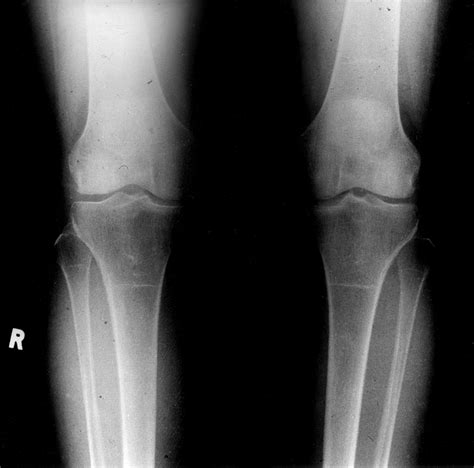

Knee Xray Normal

When you experience persistent joint pain, instability, or after a specific injury, your doctor may order imaging tests to determine the underlying cause. One of the most common diagnostic tools in orthopedics is the knee radiograph. Receiving results that describe a Knee Xray Normal finding can be both relieving and confusing, especially if you are still feeling significant discomfort. Understanding what a normal result means, how to interpret it, and what steps to take next is crucial for managing your joint health effectively.

In medical terminology, a Knee Xray Normal report means that the radiologist—a doctor who specializes in interpreting imaging studies—has examined the images of your knee and did not find any obvious signs of disease, damage, or structural abnormalities that show up on standard X-ray film. X-rays are essentially a form of high-energy electromagnetic radiation that passes through the body. Because bones and dense structures absorb more radiation than soft tissues, they appear white on the film, while softer tissues appear gray or black.

• No Fractures: There are no visible breaks or cracks in the femur (thigh bone), tibia (shin bone), or patella (kneecap).

• Intact Alignment: The bones of the knee joint are properly aligned, and there is no evidence of dislocation.

• Healthy Joint Space: The gap between the bones, which is normally filled by cartilage, appears to be of a healthy, expected width, suggesting that there is not severe, advanced osteoarthritis.

• No Abnormal Growths: There are no signs of bone tumors, cysts, or other unusual bony growths.